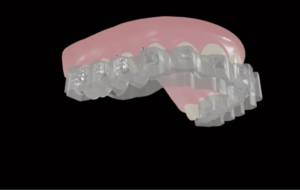

Precision du clin-check

Si vous choisissez un traitement par aligner, confiez-nous le code de votre portail fabriquant et nous vérifions vos set-up.

Car un traitement par gouttière ne se termine jamais comme montré sur la pré-visualisation. « It is not about the plastic, it’s about the plan »

Donc peaufinez vos attachements à ajouter ! et surtout sachez que dans 80% des cas il y aura besoin d’ajouter des gouttières de finition, des auxiliaires (qhx?) voire un traitement hybride (sectionnel multi-attaches puis aligners).

Augmentez votre taux de réussite avec Ortho Spirits : La planification experte qui simplifie vos traitements. Libérez tout le potentiel des aligneurs grâce à nos méticuleux services de planification de traitement. Nous élaborerons des plans personnalisés pour des résultats prévisibles, des patients plus heureux et un cabinet florissant. Stop aux retards et aux frustrations dans les traitements ! Notre équipe d’experts analyse les cas complexes, optimise les séquences d’aligneurs et vous prépare à un succès clair des aligneurs. Planifiez une consultation gratuite et découvrez comment notre planification peut profiter à vos patients et à votre cabinet.